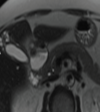

5

Q

A

Estatosis hepatica